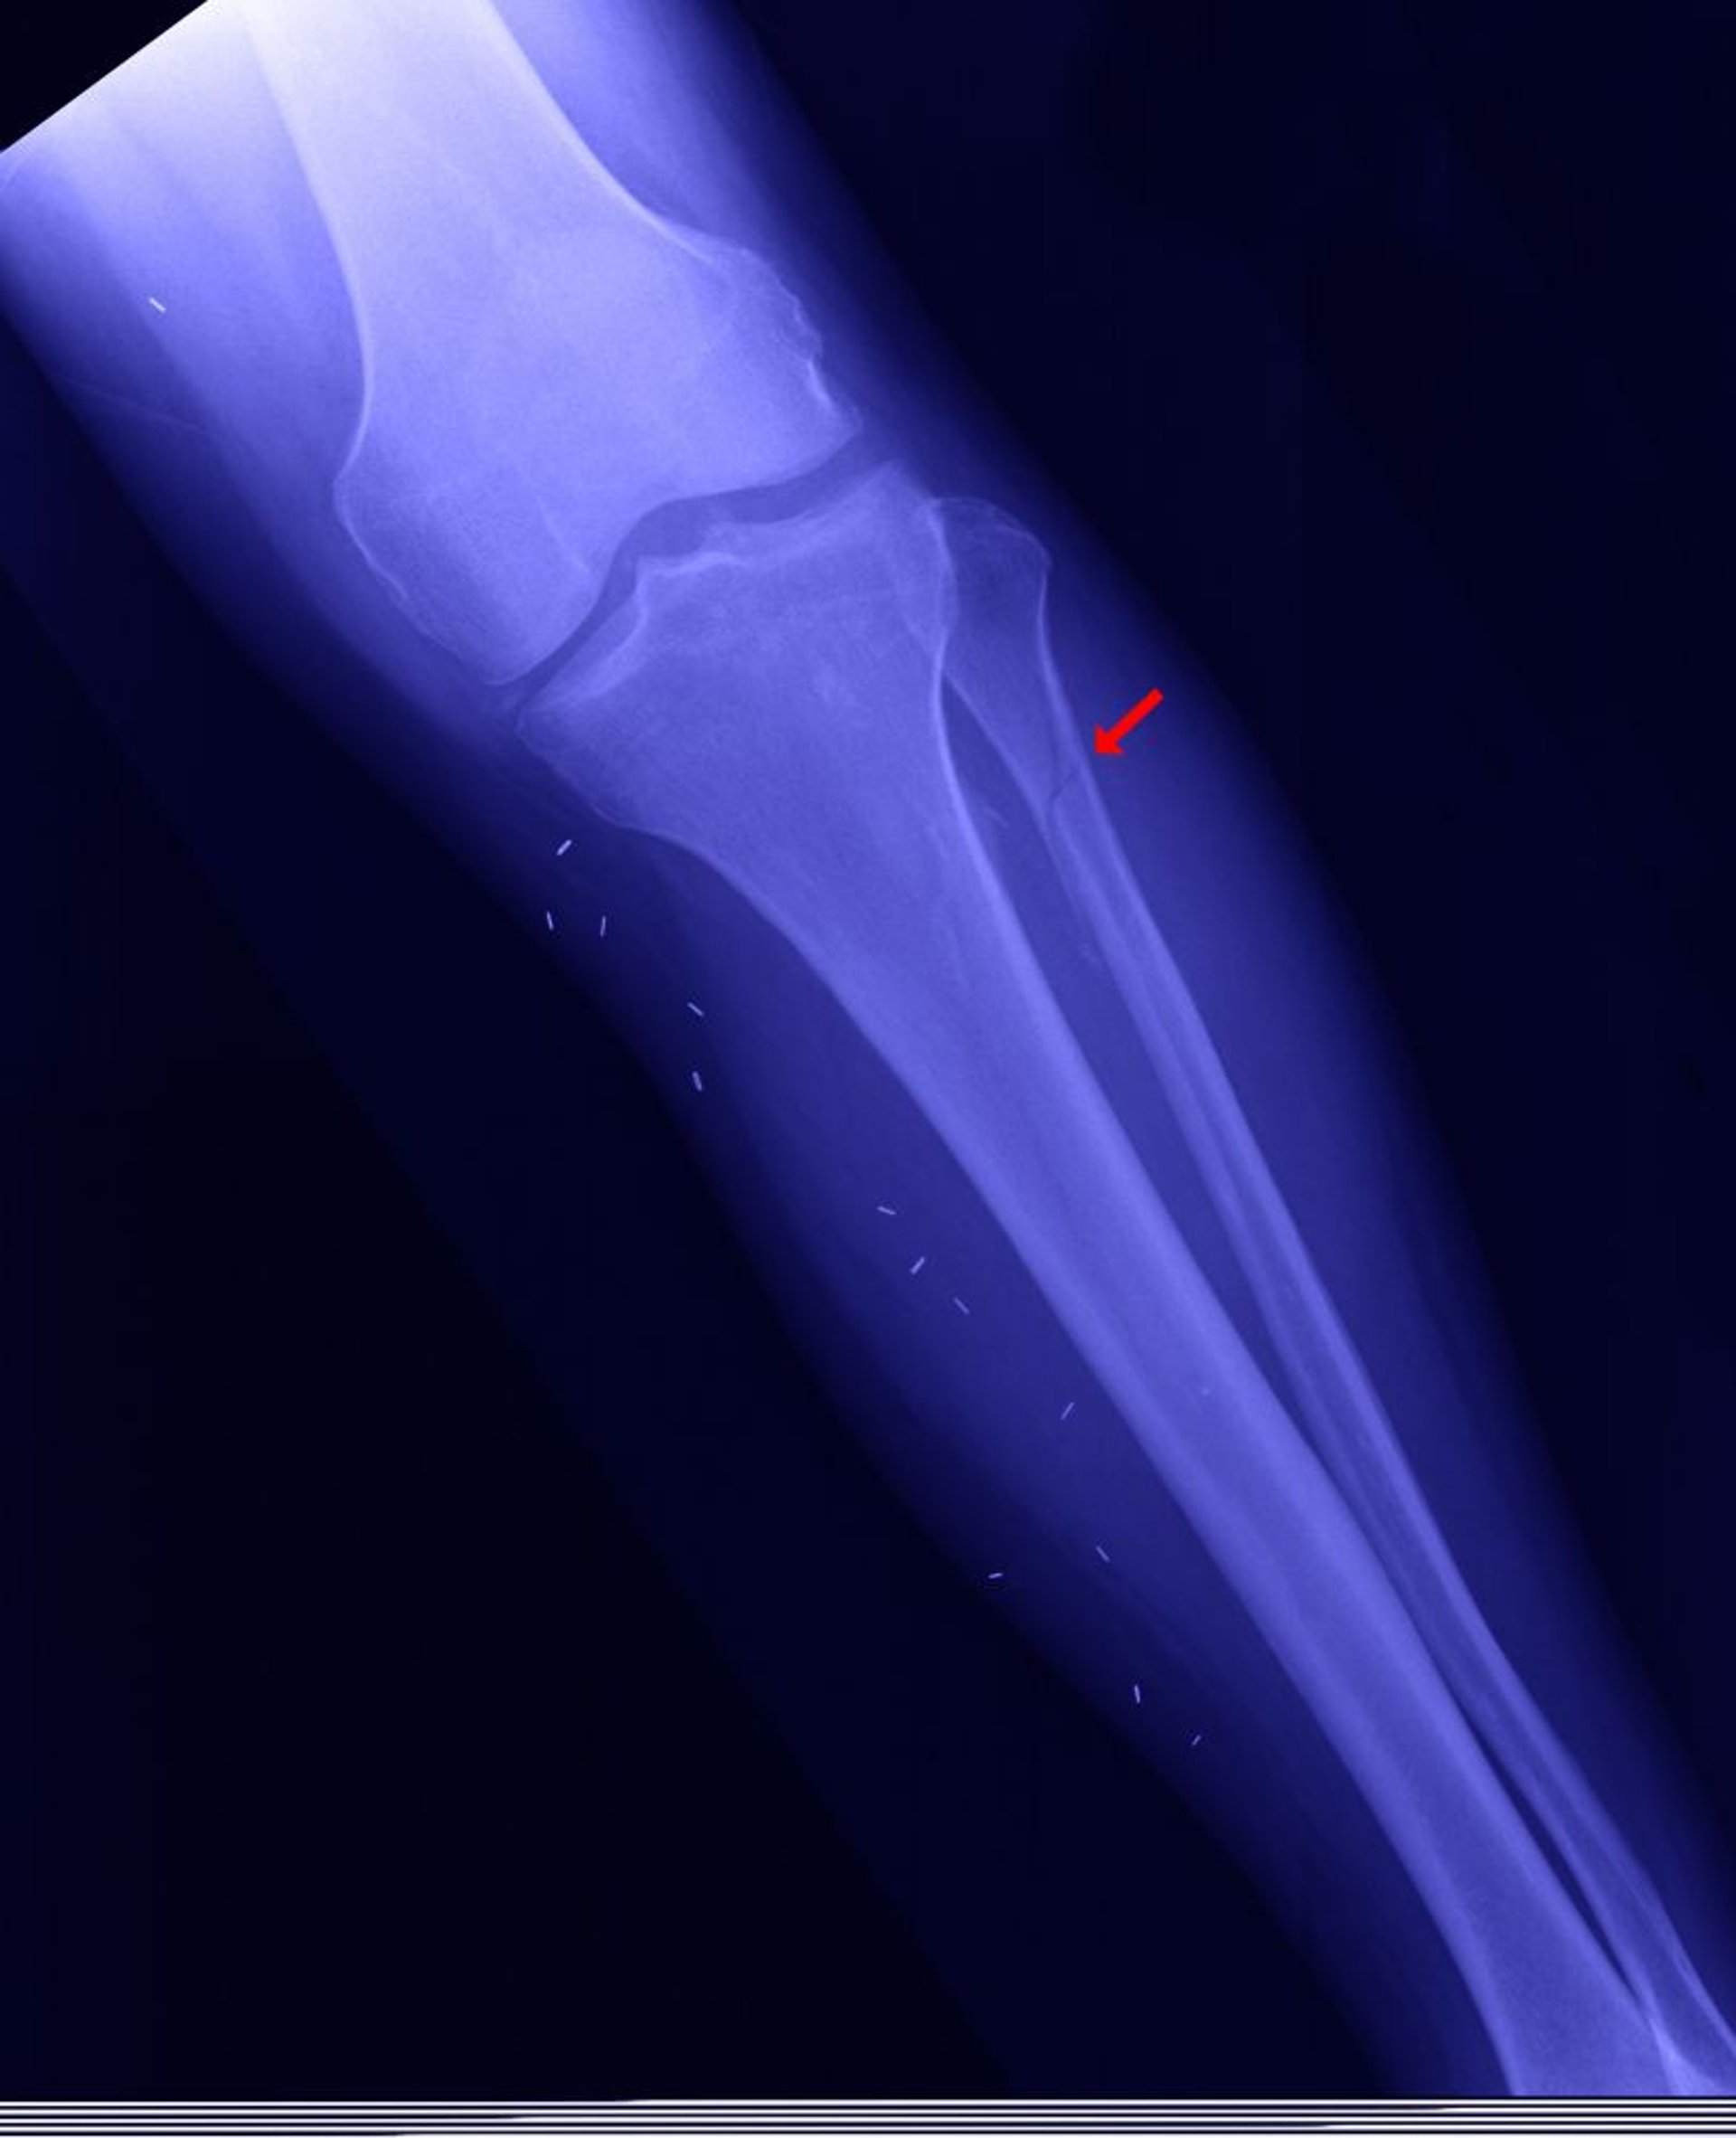

Перелом проксимального відділу малогомілкової кістки

Також можливий проксимальний перелом малогомілкової кістки (так званий перелом Мезоннева) - перелом кісточки, оголення надп'ятково-гомілкового суглоба (сполучення між великогомілковою та таранною кістками) без дистального перелому малогомілкової кістки.

ЕДВАРД КІНСМАН (EDWARD KINSMAN)/НАУКОВА ФОТОБІБЛІОТЕКА